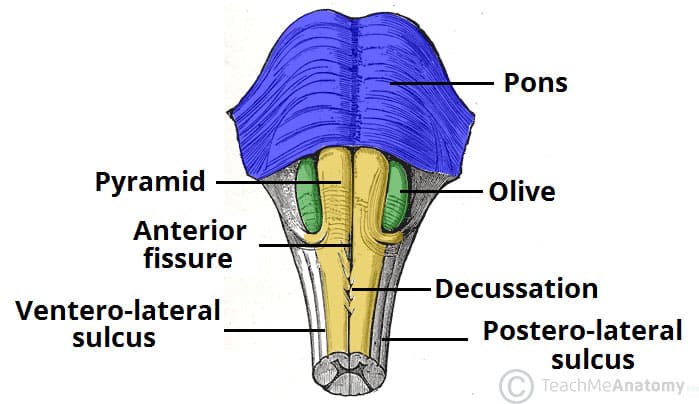

The Anatomy of the Medulla Oblongata

The Medulla Oblongata - Internal Structure - Vasculature

Figure, Medulla oblongata] - StatPearls - NCBI Bookshelf

Olives of Medulla - AnatomyZone

Surgical Anatomy of the Medulla Oblongata | SpringerLink

Brain Anatomy Medulla Oblongata And Spinal Cord Cross Section